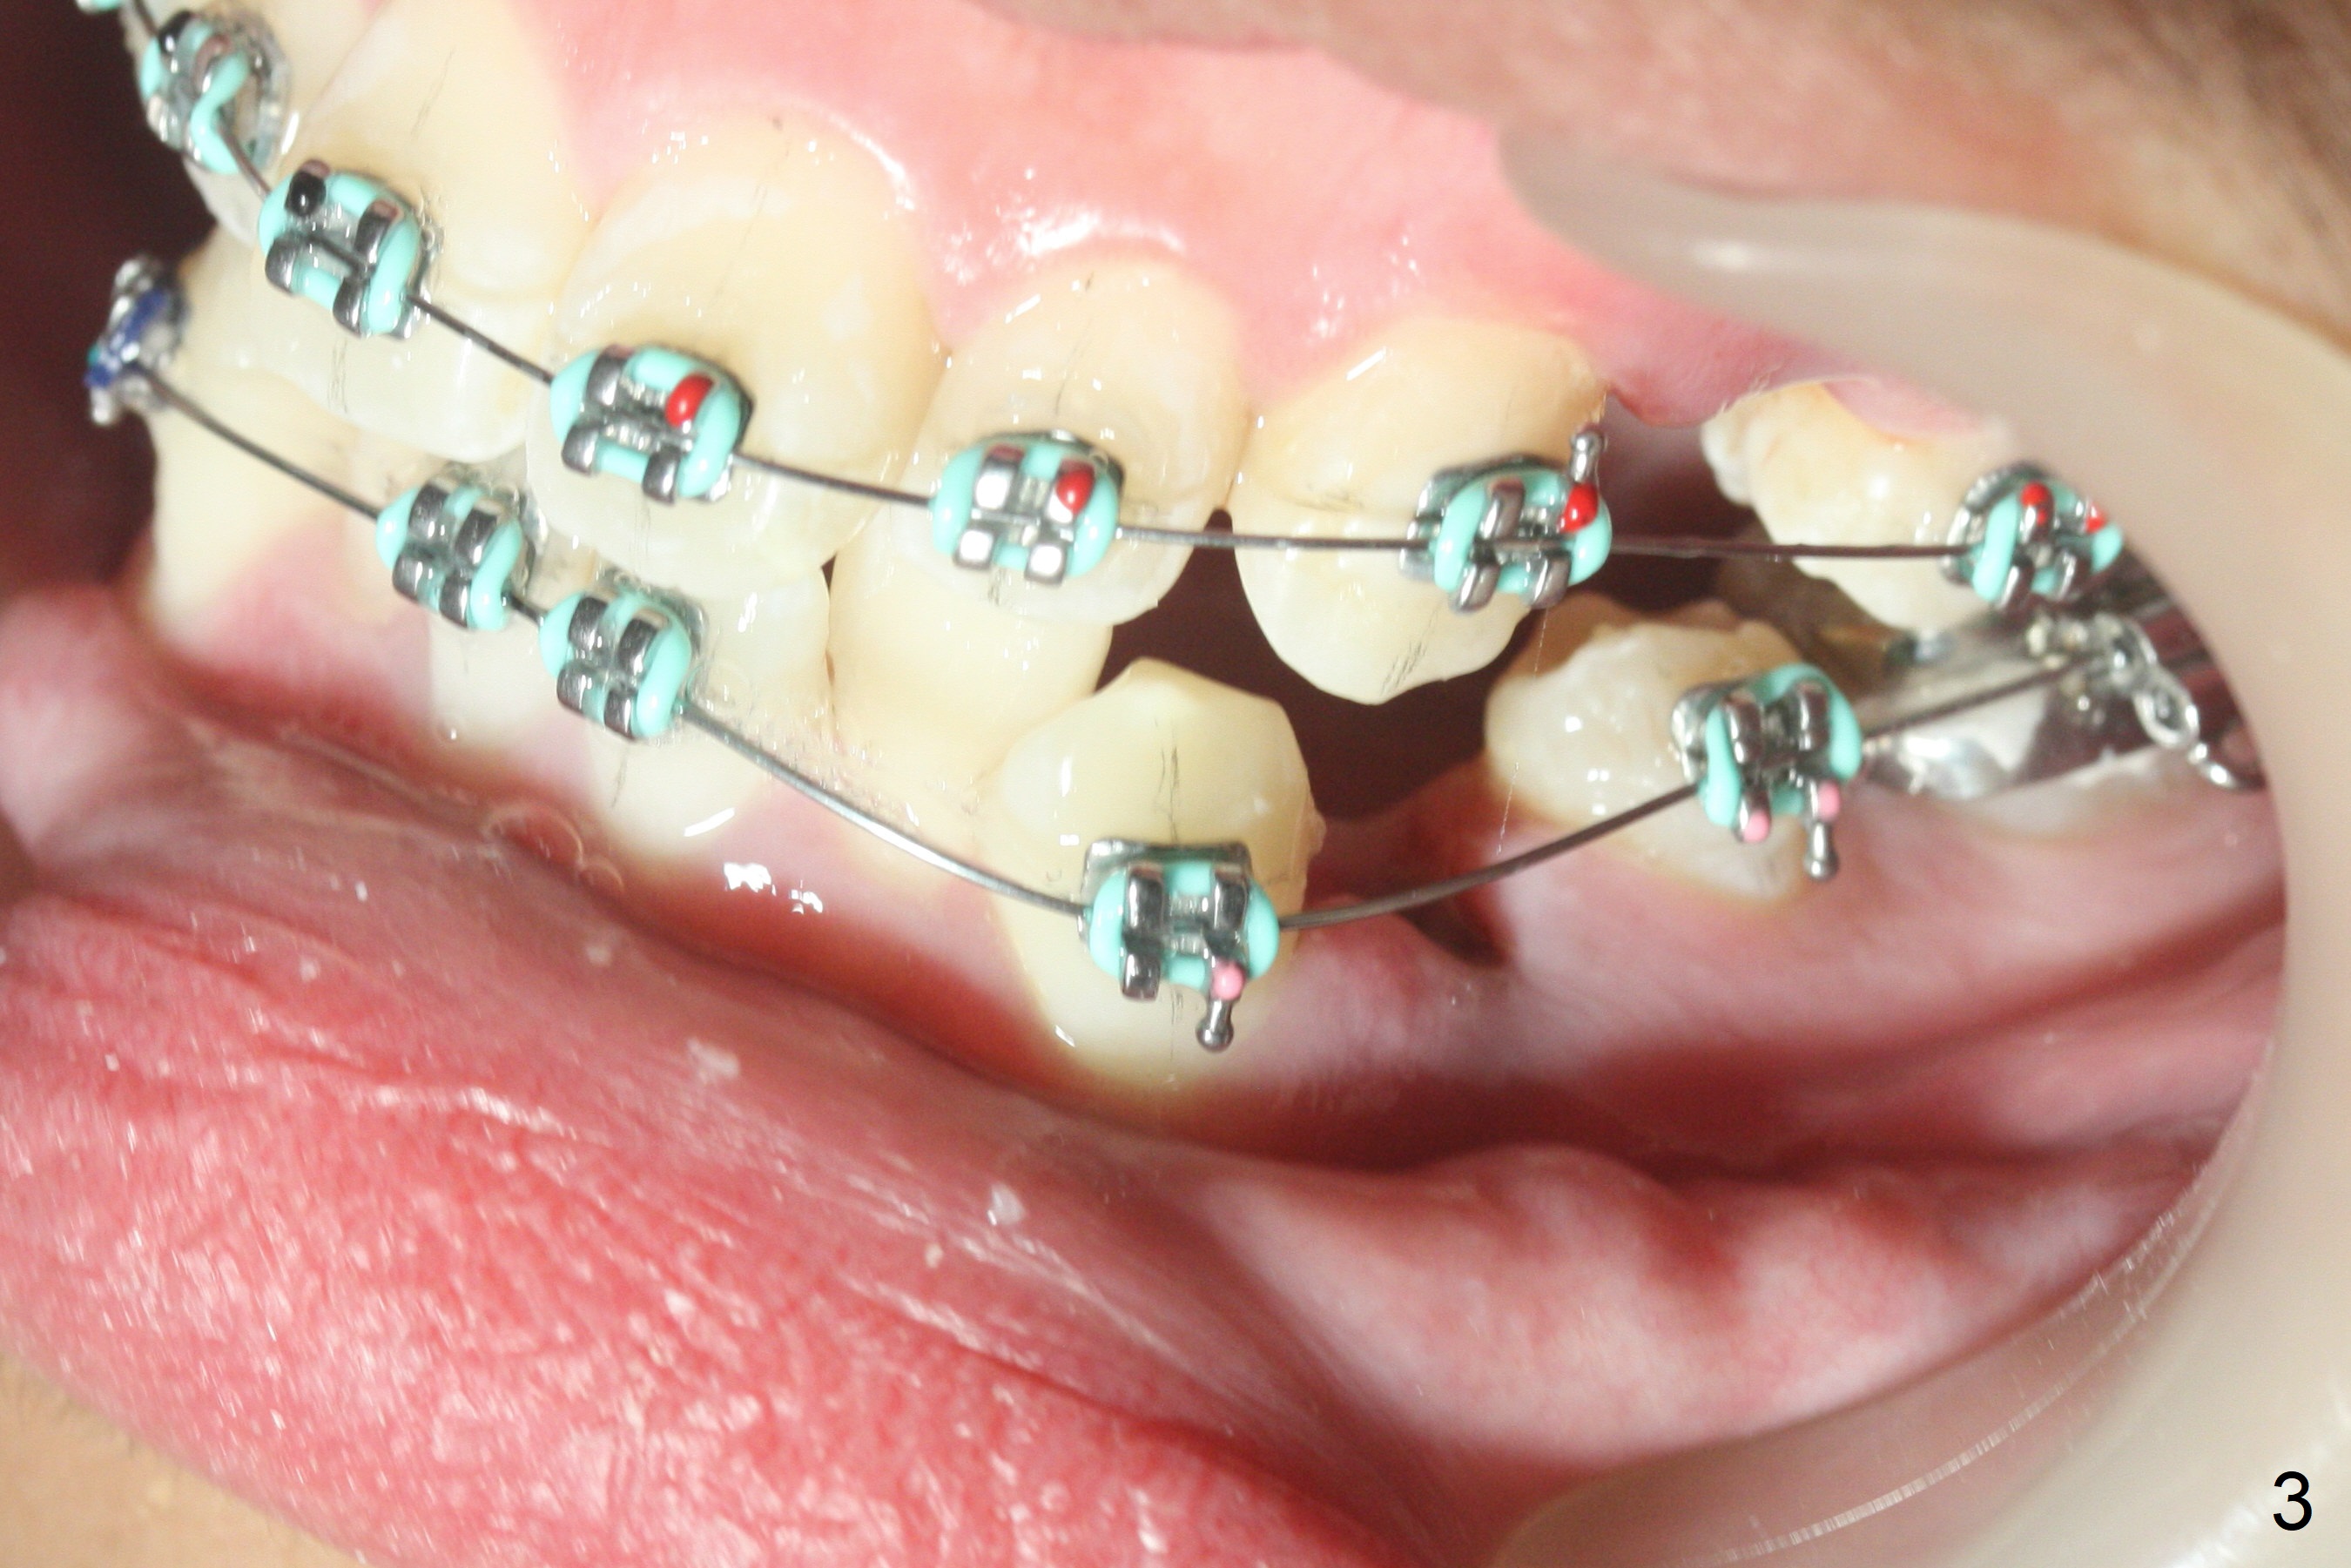

Four days post extraction of 4 of the 1st bicuspids, the patient returns for bracketing. It appears easier to place molar bands post extraction than without extraction. Spaces are larger. Anterior open bite (Fig.1-3) is due to premature contact of the mesiobuccal cusp of UR7 and the buccal tube at LR 7. To facilitate LR3 distalization, power chains are placed between LR3 and 6 (Fig.1 .014 niti wires), while tension in LL seems to be too high for power chains (Fig.3). The lower wire dislodges from the 2nd molar bands twice in 2 weeks; it appears that LR3 has been distalized (Fig.4); to reduce the chance of wire displacement, power chains x 5 are to be placed in LL 3-7 as well.